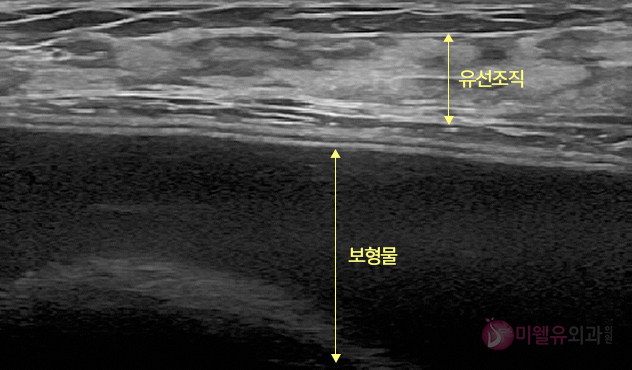

정상 보형물 초음파